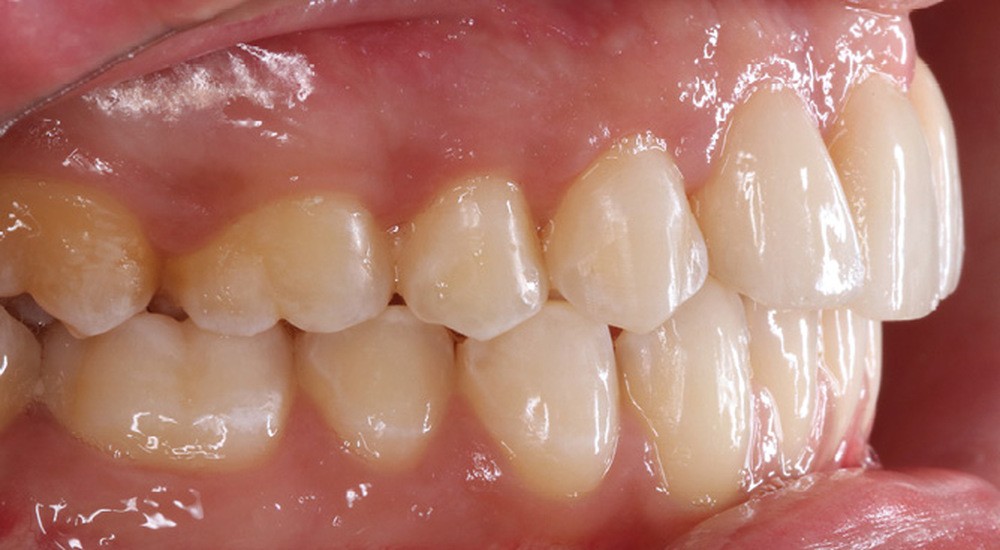

Antony, 11 ans se présente initialement pour une demande esthétique concernant ses deux incisives centrales qu’il trouve trop grosses (fig. 1a-c).

Le profil est convexe et associé à une inocclusion labiale au repos. Il s’agit d’une classe II squelettique sur un schéma facial normodivergent. Les rapports occlusaux sont de classe II bilatérale (complète au niveau molaire) avec des incisives inférieures vestibulo-versées. La 21 est géminée et la 11 vraisemblablement fusionnée avec un germe surnuméraire, sans altération de la formule dentaire. Du fait du diamètre mésiodistal fortement augmenté des incisives centrales, et du manque de place à l’arcade maxillaire qui en découle, les 12 et 22 sont en inversé d’occlusion en palato position. Les 53 et 63 sont persistantes sur l’arcade avec une inclusion en transposition incomplète de la 13, dont la cuspide se situe entre la racine de la 12 et celle de la 11 résorbée (fig. 1d-g).